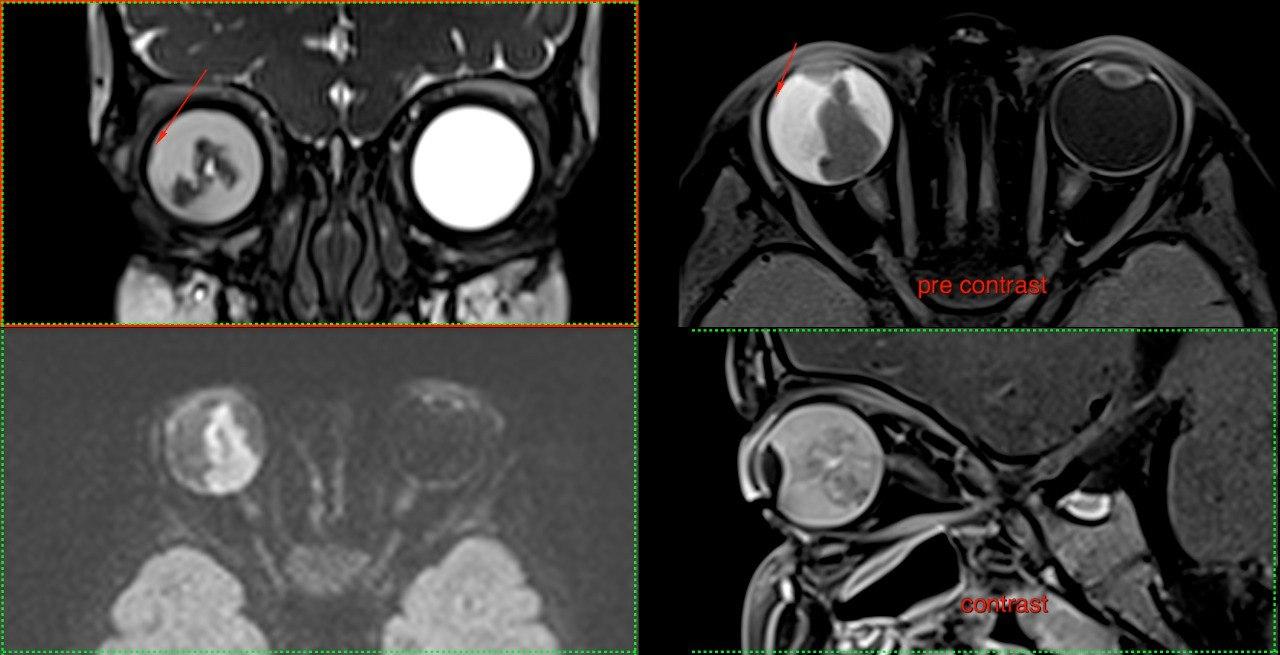

- МРТ: Створює найчіткіші зображення м’яких тканин, органів та судин. Без використання шкідливого випромінювання, тому також підходить для візуалізації вагітних, дослідженні плоду.

У нас є можливість проведення досліджень високої роздільної здатності всіх органів та систем (за винятком серця), зокрема в складі синдромів/комбінованих вадах. Обстеження виконуються, як для дітей так і дорослих пацієнтів, в т.ч. з анестезіологічним забезпеченням (седація, наркоз).

Завдяки передовим технологіям ми маємо можливість проводити МРТ дослідження “всього тіла” (whole body)*, мультипараметричні обстеження головного мозку та простати з наявними програмами МР-трактографії (DTI), МР-спектроскопії, також виконуємо безконтрастну МР-ангіографію інтракраніальних судин, шиї; МР-холангіопанкреатографію, ентерографію, визначення перенавантаження залізом печінки.